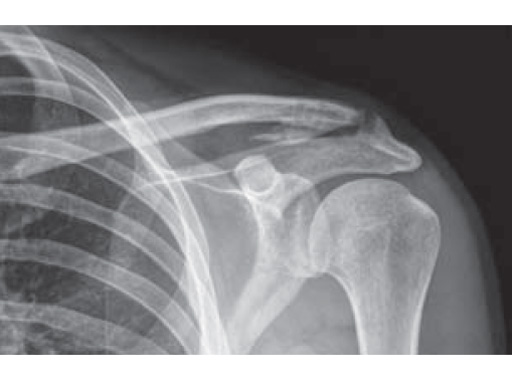

Fig.

Preoperative x-rays